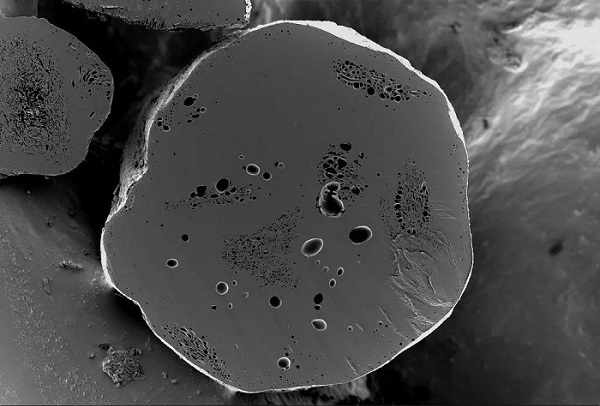

缓释药颗粒内部孔隙结构观察